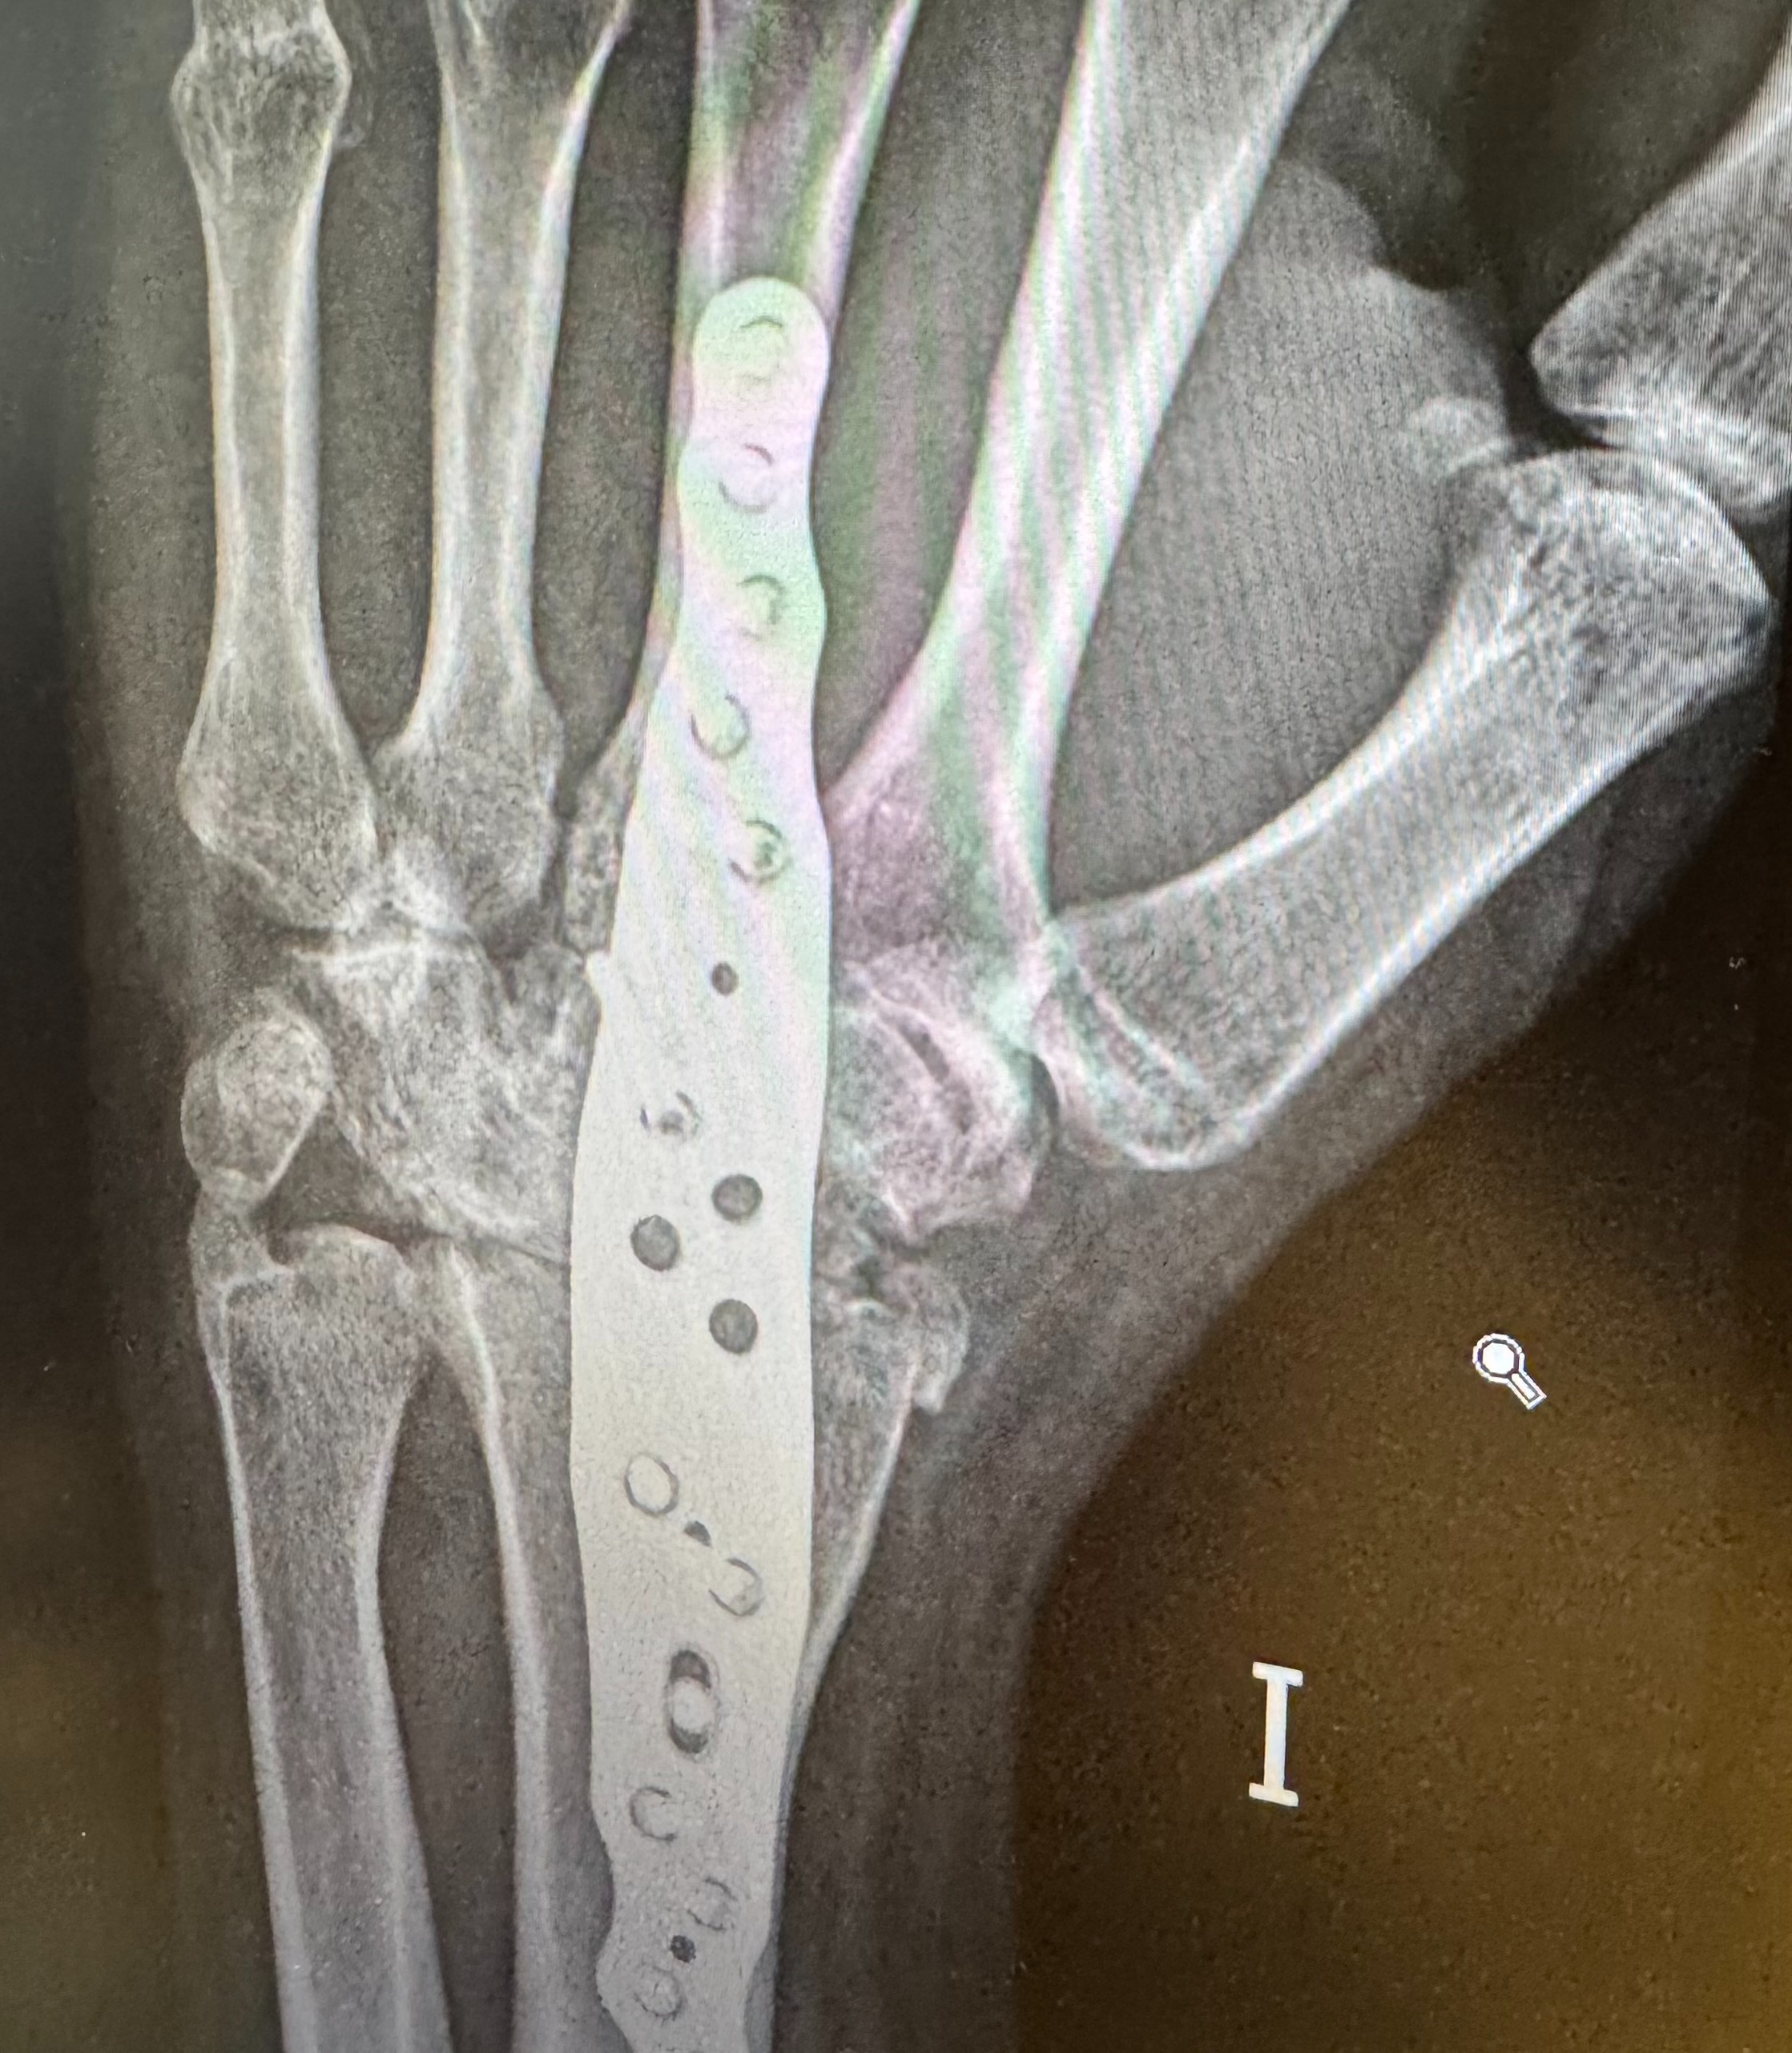

En marzo de 2024, decidido a terminar con mi vida, un amigo me convenció de ver a un especialista. Ahí descubrieron que llevaba 31 años con la muñeca rota: una simple operación resolvía gran parte del problema. La pregunta es inevitable: ¿cómo nadie lo vio antes? ¿Cómo se permitió tanto encubrimiento, soborno y abandono?